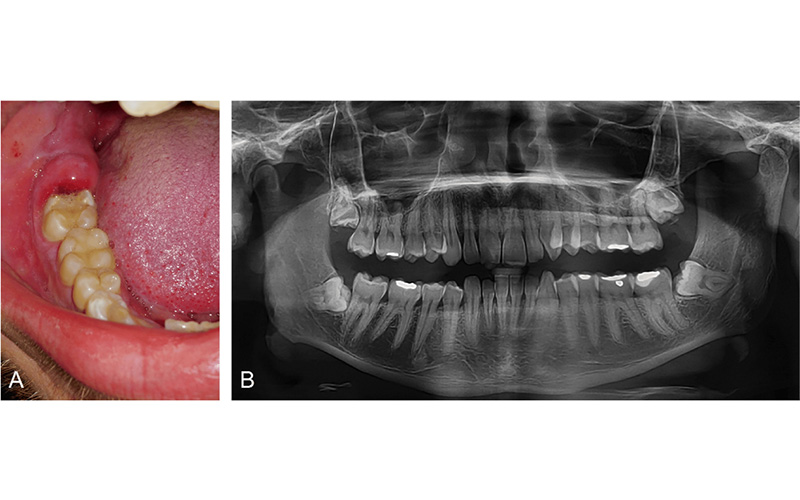

پریکرونیت به دو نوع حاد (ناگهانی و شدید) یا مزمن (خفیف اما مداوم) ظاهر می‌شود. در موارد شدید، تب و لرز (که نشانه گسترش عفونت است)، درد شدید در گوش و گلو یا تورم شدید و مشکلات تنفسی ممکن است به علائم زیر اضافه شود.

• درد و التهاب لثه اطراف دندان عقل

• قرمزی و تورم لثه (به خصوص در ناحیه ای که دندان عقل در حال رشد است)

پریکرونیت یا عفونت دندان عقل به التهاب لثه های اطراف دندان عقل گفته می شود که تا حدی پنهان است و به طور کامل از لثه خارج نشده است. این وضعیت زمانی رخ می دهد که باکتری ها، بقایای غذا و پلاک در اطراف دندان عقل گیر کرده و باعث عفونت و التهاب لثه ها می شود. پریکرونیت بسیار شایع است و بسیاری از افراد 17 تا 25 ساله اشکال خفیف یا شدید آن را تجربه می کنند.

4. پریکرونیت چگونه تشخیص داده می شود؟

عفونت دندان عقل با معاینه دندانپزشکی و در برخی موارد تصویربرداری با اشعه ایکس برای بررسی موقعیت دندان عقل تشخیص داده می شود.